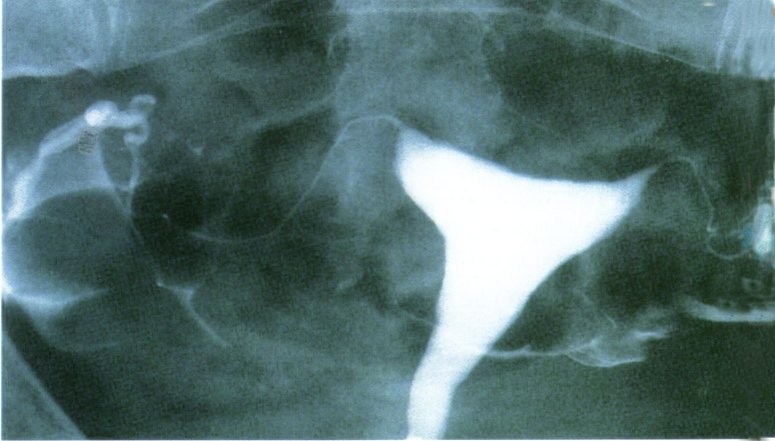

Hystérographie :

L'hystérographie consiste à injecter un produit opaque aux rayons X par le col de l'utérus et à visualiser son passage dans les trompes.